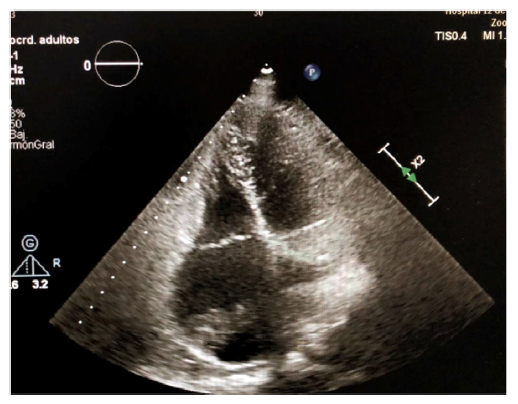

Varón de 70 años de edad, quien acudió a urgencias por episodio vasovagal con hallazgo incidental de fibrilación auricular con respuesta ventricular controlada, que se trató de manera ambulatoria mediante anticoagulación oral con acenocumarol. Durante el control ambulatorio, dos meses después, se hizo ecocardiograma transtorácico en el que se evidenció masa auricular derecha de gran tamaño (fig. 1), motivo por el cual fue ingresado. Se completó el estudio con un ecocardiograma transesofágico que reportó dos masas contiguas (32x18mm y 16x22mm) en la desembocadura de la vena cava inferior, dependientes de la válvula de Eustaquio, que atravesaban la aurícula derecha y alcanzaban el septo interauricular sin comprometer la función de la válvula tricúspide (figs. 2 y fig 3). Como primera posibilidad diagnóstica se planteó un mixoma auricular y ante la posibilidad de embolización se optó por manejo quirúrgico, no sin antes efectuar una coronariografía, que no reportó lesiones; se programó para resección del mixoma. Durante la cirugía se hallaron dos masas de aspecto fibroelástico (fig. 4 ) que no se relacionaban con el septo y que al ser resecadas no alteraban la competencia de la válvula tricúspide. La cirugía y el postoperatorio cursaron sin complicaciones y el estudio anatomo-patológico informó que las masas correspondían a trombos, sin hallazgos de componente tumoral. Durante el seguimiento a seis meses permanecía asintomático y en ritmo de fibrilación auricular.

Figura 1 Ecocardiograma transtorácico en proyección de cuatro cámaras, en el que se observan las dos masas en la aurícula derecha.